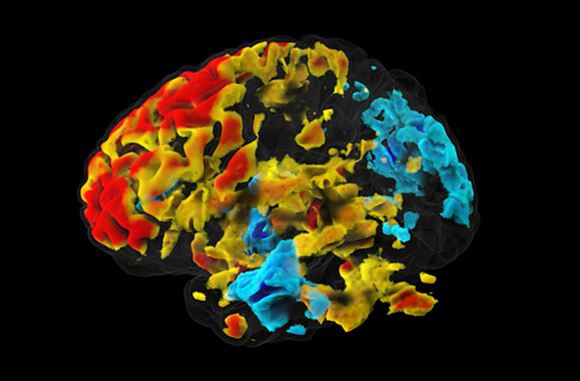

עבור כל ווקסל נרצה לבחון אם היה שינוי באות בזמן ביצוע המטלה, לעומת רמת האות שנמדדה בתנאי הביקורת. מוח ועליו מסומנים ווקסלים שמעלים את פעילותם (בגוונים חמים) ואלו שמורידים את פעילותם (בגוונים קרים) כאשר נבדקים הזדהו עם רגשות של אחרים | התמונה באדיבות ד”ר עדי יניב